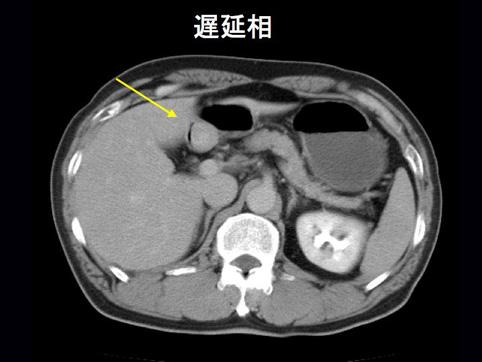

A case of carcinoid tumor which developed in the duodenal bulb.

[Image-ID:11493]

카시노이드종양/

십이지장/구부

CT

1형(종괴형)/

15~19